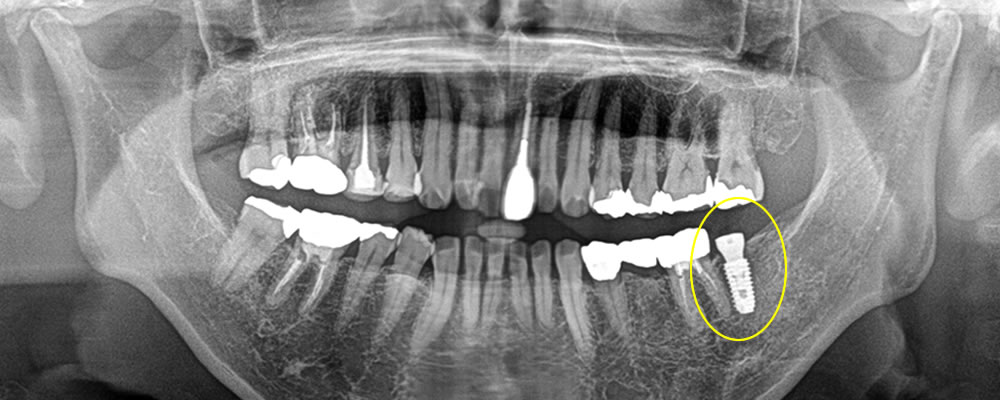

インプラント手術の実施

事前の精密検査を実施し、計画通りの位置へインプラントを埋入しました。

上部構造の装着・治療完了

顎骨とインプラントの結合期間を経て、製作した上部構造を装着し、咬み合わせを調整した治療完了となりました。

インプラント埋入後は治療前よりも奥歯でものを噛むことが出来るようになり、左右で均等に噛めるようになりました。今は歯周病やむし歯の予防のために、定期的なクリーニングで通院していただいております。